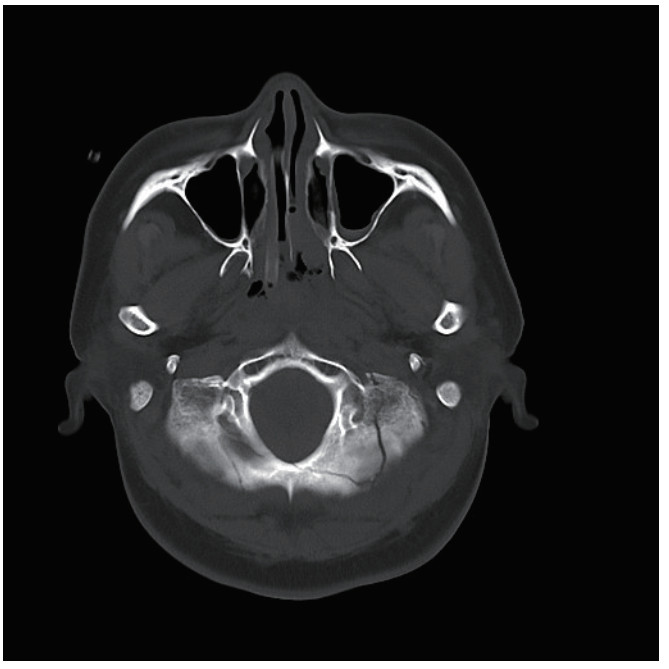

1 病例资料患者,女性,40岁,因“车祸致全身多处外伤半小时余”于2025年6月27日由120送入黄山市人民医院急诊。患者2 h前骑电瓶车发生车祸,致头面部、胸部及左下肢严重受伤,当即昏迷,伴恶心呕吐。入抢救室时自主呼吸微弱,后出现室速,伴随血流动力学不稳定,GCS评分为6分(E1V1M4),双侧瞳孔不等大、对光反射迟钝,左侧直径3 mm,右侧5 mm,后枕部头皮血肿,左下肢胫腓骨区域明显肿胀畸形。医院立即实施全面评估,经紧急行电复律、利多卡因静推后恢复自主心率,予以气管插管保护气道,建立深静脉通路泵入血管活性药物维持血压、纠正酸中毒。完善CT检查:双侧脑挫伤、创伤性蛛网膜下出血、右侧额顶部硬膜下血肿,中颅底及枕骨骨折、累及枕骨大孔,左侧胫腓骨骨折及双肺坠积性改变。见图 1,2。神经外科会诊诊断为弥漫性轴索损伤,无立即手术指征,收入EICU监护稳定生命体征。

| 图 2 枕骨骨折 |